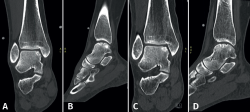

Fixation techniques have shown clinical and radiological success in 8 out of 10 patients, also maintaining their success in the long term (Figures 5 and 6). As these techniques preserve the hyaline cartilage and provide superior healing of the subchondral bone, they are advantageous over other surgical treatment options for OLTs, when feasible(39,41).